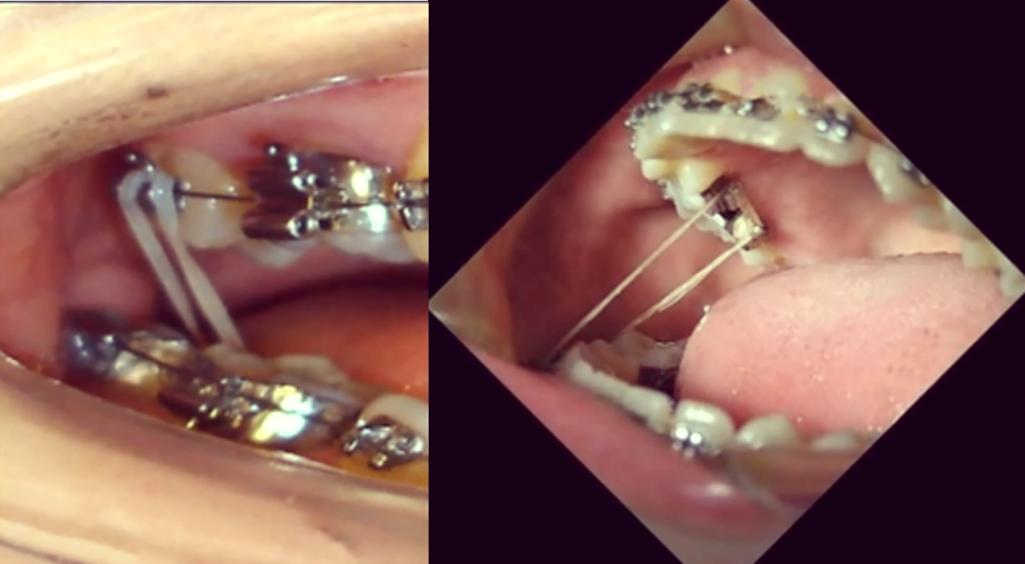

- 橡皮筋: 最常用,将橡皮筋一端挂在尖牙托槽的牵引钩上(或粘在尖牙上的牵引钩上),另一端挂在后牙(如磨牙)的带环或托槽的牵引钩上,通过选择不同的挂钩位置和橡皮筋类型(力量、方向),实现向下向后的合力。

- 正畸丝: 使用特定的弓丝弯制(如摇椅弓、关闭曲等),利用弓丝的形变力量移动牙齿,有时需要配合颌间牵引(上下牙之间挂橡皮筋)。

- 托槽: 粘在尖牙上的托槽通常带有牵引钩。

- 额外牵引钩: 有时需要在尖牙牙面额外粘一个小的牵引钩,以便于挂橡皮筋。

- 拉钩: 对于埋伏牙牵引,外科暴露后,医生会在牙冠上粘一个金属拉钩(通常是“眼睑拉钩”或“骨钩”),用于连接牵引装置。